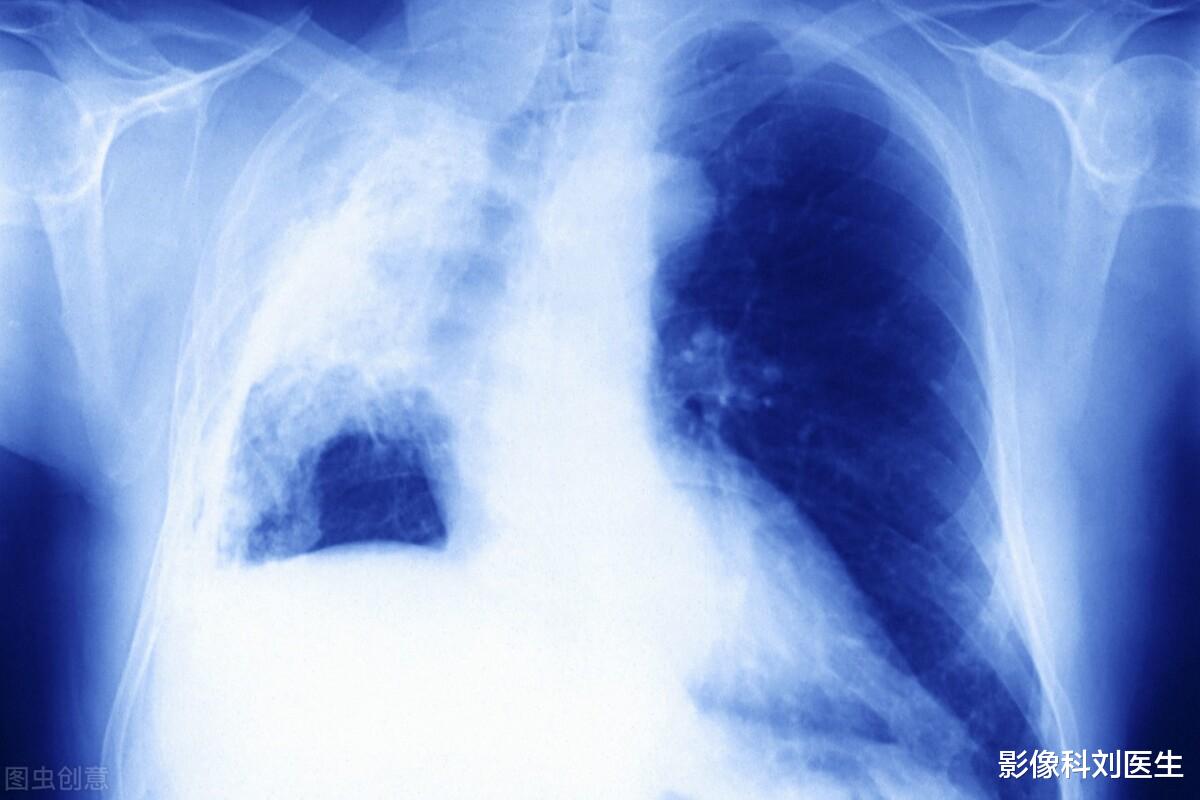

如何才能早期发现肺癌?对于早期肺癌的诊断 , 刘医生推荐大家做一种检查 , 也就是胸部CT扫描 。 胸部CT扫描可以说是诊断肺癌最为重要的方法 , 特别是对于早期微小肺癌的发现和诊断 , 它有着不可取代的作用 。

而如果是体检筛查 , 建议大家可以选择胸部CT扫描中的低剂量螺旋CT扫描 , 低剂量螺旋CT扫描相对于普通CT辐射剂量更低 , 大约只有普通CT辐射剂量的1/5左右 , 它对于人体的辐射损伤几乎可以忽略不计 , 大家可以放心地去做;同时低剂量螺旋CT它对于肺结节和早期肺癌的观察并没有太多的影响 , 所以是非常好的一种检查方法 。

而像胸片检查、磁共振检查、抽血检查等其他的辅助检查方法 , 对于早期肺癌的筛查并不准确 。

总结【影像科刘医生|肺癌的发生和哪些因素有关?如何才能早期发现肺癌?】对于肺癌 , 早发现、早诊断、早治疗是非常重要的 , 所以刘医生建议上述有相关高危因素的人群 , 可以每年做一次胸部CT检查 , 及时有效的筛查肺结节和早期肺癌 , 如果怀疑有恶性征象 , 及时进行手术切除治疗 , 如果早期肺癌治疗及时 , 往往都是可以取得非常不错的治疗效果的 。